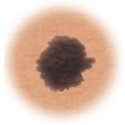

Lunares (nevos)

Son marcas pequeñas en la piel que se deben a las células que producen el pigmento. Los lunares pueden ser planos o elevados, lisos o ásperos y algunos tienen pelos. La mayoría es de color marrón oscuro o negro, pero algunos son amarillentos o del color de la piel. Los lunares pueden cambiar con el tiempo y a menudo reaccionan a los cambios hormonales.

En la mayoría de los casos, los lunares son benignos y no se necesita tratamiento. Algunos lunares benignos pueden convertirse en cáncer de piel (melanoma). A continuación puede consultar los signos de que un lunar se está volviendo canceroso.

Lunares atípicos (nevos displásicos)

Los lunares atípicos son más grandes que los normales (tienen más de media pulgada o 1.25 cm de diámetro) y no siempre son redondos. Pueden ser de color marrón claro u oscuro, con un fondo rosado. Estos lunares pueden presentarse en cualquier parte del cuerpo.

El tratamiento puede incluir extirpar cualquier lunar atípico que cambie de color, de forma o de diámetro. Además, las personas con lunares atípicos deben evitar la exposición al sol, ya que la luz solar puede acelerar los cambios en este tipo de lunares. Quienes los tienen deben consultar con un proveedor de atención médica sobre cualquier cambio que pueda ser indicio de cáncer de piel.